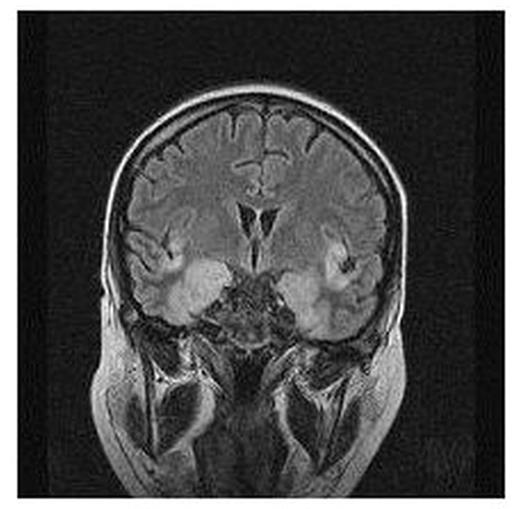

Patients: A 35-year-old female with relapsed multiple myeloma, underwent alloHSCT from a matched unrelated donor (MUD). On day +120, she developed an acute onset of fever, drowsiness, and generalized seizures. After 48 hours, a rapid deterioration of neurological symtoms was observed and the brain MRI showed acute encephalitis with high signal intensity in the temporal lobe and insula cortex (fig. 1). The HSV-PCR from cerebrospinal fluid (CSF) was positive for HSV-1, and a treatment with acyclovir 30 mg/Kg/d was initiated, 72 hours after the hospital admission. A 66 year-old male with high risk AML underwent MUD alloHSCT. Thirteen months after transplant, an acute sialoadenitis and HSV-1 gengivostomatitis occurred, followed by fever and focal seizures. Since typical lesions of HSE were demonstrated by brain MRI, antiviral therapy with aciclovir was promptly administrated, within 24 hours from the symptoms onset. HSV-PCR on CSF was performed two days later, and proved negative, probably due to ongoing antiviral therapy and delay to CSF analysis. After 21 days of antiviral treatment, both patients recovered from the acute phase, but in the first case we observed serious neurological sequelae that required prolonged unsuccessful cognitive rehabilitation. The second patient didn’t experienced significant residual neurological impairment, and didn’t require any other supportive measure. Both pts have had chronic GVHD and received prolonged courses of immunosuppressive therapy; they experienced recurrent CMV infections thereafter, and were under high dose foscarnet therapy at the diagnosis of HSE, but without HSV prophylaxis.